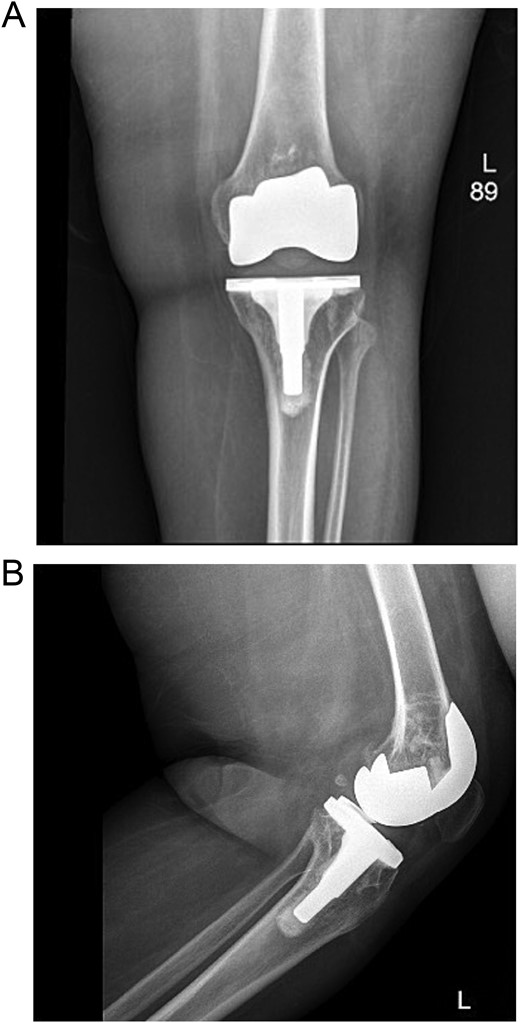

Upon examination in the emergency room, the patient was vitally stable, alert, and oriented. Her skin was intact, showing a healed wound. Mild swelling was noted over the left knee joint, with no erythema or ecchymosis. She had tenderness over the medial surface of the knee. The active ROM was from 0º to 90º and was limited due to pain; the passive ROM was from 0º to 110º with a clicking sound during flexion. Soft compartments were noted, and distal neurovascular examination was unremarkable (Fig. 2).

(A) Anteroposterior view of the left knee in the emergency department. (B) Lateral view of the left knee in the emergency department.